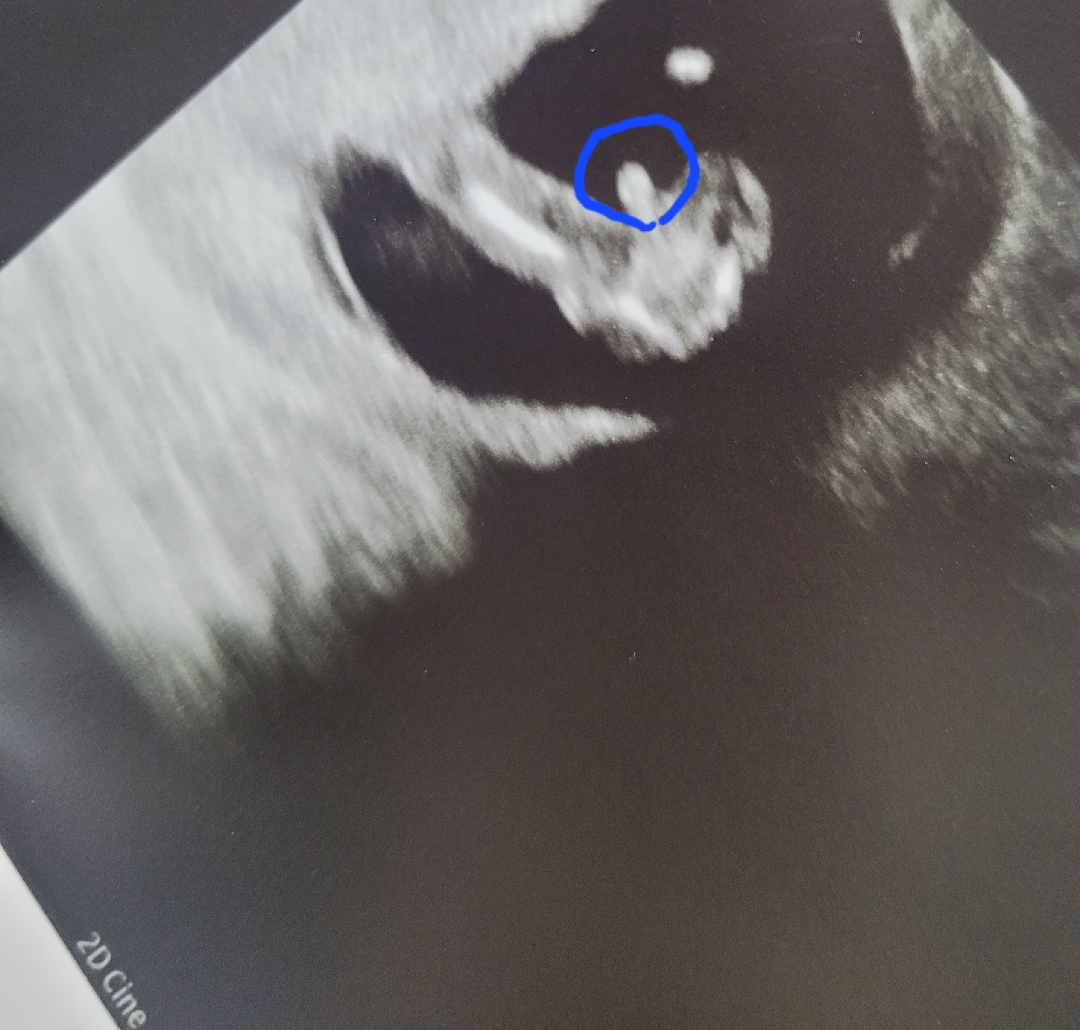

12주 4일 다리사이..아들일까요

12주 4일에 다리사이에 타원형 무언갈 보고왔어요ㅎㅎ 아들 맞을까요 ㅎㅎ 없어질수도있을까요..? 시기가 이른감이 있어서요